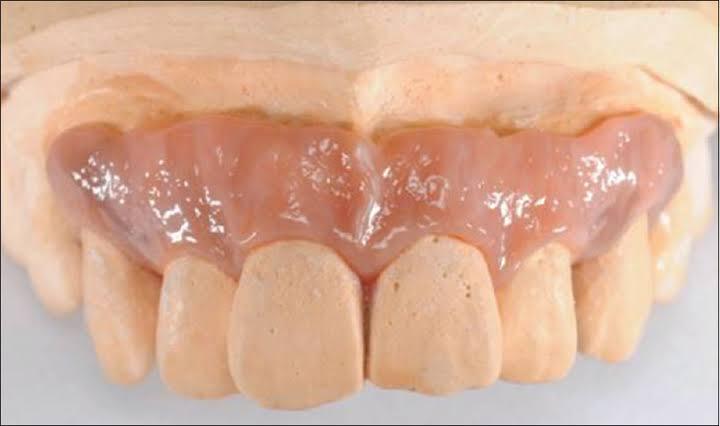

- Gusi yang mengalami penurunan (resesi) perlu dilakukan perawatan. Dokter gigi akan mengawali perawatan dengan melakukan pembersihan karang gigi dan penghalusan akar gigi yang terekspos / tidak tertutup lagi oleh gusi. Apabila tulang penyokong gigi dan gusi ini mengalami kehilangan / penurunan tinggi tulang yang ekstrim maka pembersihan dilakukan dengan membutuhkan pembedahan agar alat dapat mencapai saku gusi yang lebih dalam lagi. Setelah dilakukan pembersihan plak dan karang gigi pada permukaan luar gigi, akar gigi, dan saku gusi untuk memperbaiki estetika dapat dilakukan berbagai cara seperti gingivoplasty, gingival graft, dan artificial gingiva. Gingivoplasty adalah suatu prosedur pembedahan yang dilakukan untuk memperbaiki bentuk dan kontur gingiva. Gingival graft / cangkok gusi merupakan prosedur untuk memperbaiki penampilan gusi yang turun dengan menambahkan jaringan gusi pada daerah yang mengalami penurunan gusi. Jaringan gusi yang digunakan dapat diambil dari gusi di sekitar daerah tersebut atau mengambil sebagian gusi dari langit-langit mulut. Sedangkan artificial gingiva adalah gusi tiruan yang terbuat dari bahan silikon. Lakukan kunjungan rutin ke RSGMP Nala Husada minimal 6 bulan sekali.